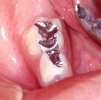

2-1.インレー修復(虫歯の穴に金属を装着する治療法)

虫歯を削った穴の型を取って模型を作り、それに合うように鋳造した金属をセメントで歯に装着します。噛む力のかかりやすい場所にできた虫歯に対する代表的な治療方法です。

3-3.乳歯冠(乳冠歯銀歯のかぶせもの)

治療済みの歯の大きさに合わせた既成の銀歯を選びかぶせます。はえかわるときに歯と一緒に抜けます。